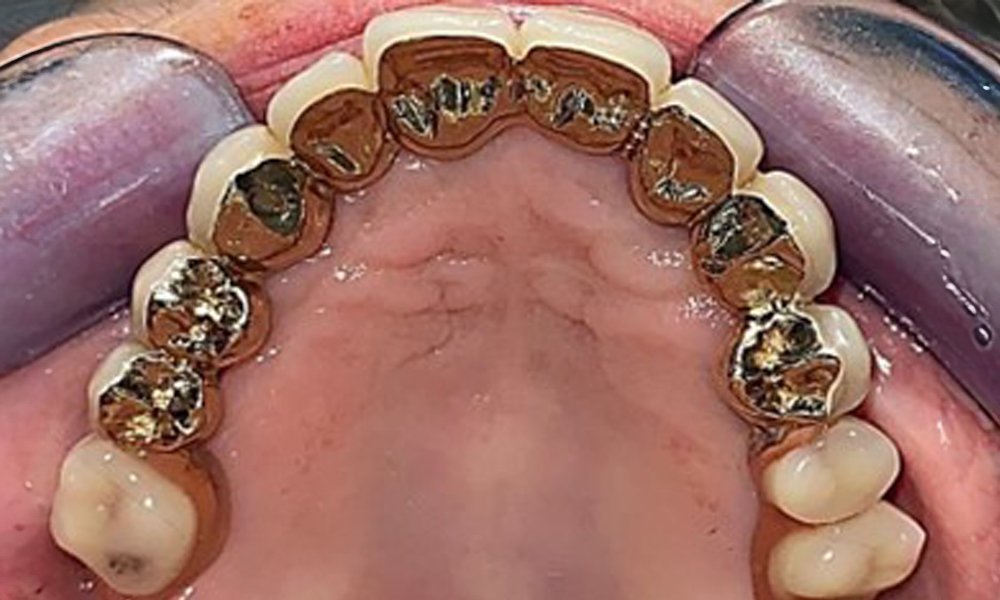

Okklusalansicht: Oberkiefer mit Zahn- und implantatgetragenen Teleskopen.

Abb. 2: Okklusalansicht: Oberkiefer mit Zahn- und implantatgetragenen Teleskopen.

Dentaler Befund

Der dentale Befund stellt sich wie folgt dar: Kombinierte herausnehmbare Implantat- und zahngetragene Teleskoparbeit auf Implantaten 15, 13, 21, 23, 24, 25 und Zahn 11 (Abb. 1, Abb. 2, Abb. 3). Im Unterkiefer ist die Patientin mit einem festsitzenden Zahnersatz versorgt. 37–34 sowie 45–47 haben suffiziente Brücken (Abb. 4). Kronenränder sind intakt, aktive kariöse Läsionen sind nicht vorhanden. An Zahn 43 zeigt sich eine Compositefüllung mit Randspalt. Im Unterkiefer liegen Rezessionen mit freiliegender Wurzeloberfläche zwischen 1 – 3 mm vor. Dies trifft auch für 11 zu.